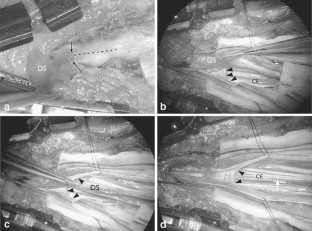

Cases of infected dermal sinus are scarce and detailed surgical anatomical descriptions are hardly found in literature. The clinical, radiological, and surgical findings in four cases of an infected dermal sinus located at the lower spine are presented to elucidate the pathological anatomical configuration.

The first case showed two dermal sinuses with a parallel course extra- and intradurally, ending in a confluence of cavities connected to the conus. In this case, as well as in the fourth case, the signs and symptoms were those of meningitis. The second case presented with meningitis and a subdural empyema, while the third case presented with an intradermoid–intramedullary abscess at the junction between the DS and the conus. This child probably showed signs and symptoms of conus involvement as early as during pregnancy.

The anatomy of the nervous elements in this congenital anomaly is heavily disturbed, more particularly in case of infection, due to extensive arachnoidal scarring. The latter renders dissection laborious and recognition of anatomical details difficult, resulting in complete excision of a dermal sinus in less than half of the cases. Despite their variability in presentation, most cases of an infected dermal sinus show similar characteristic features.